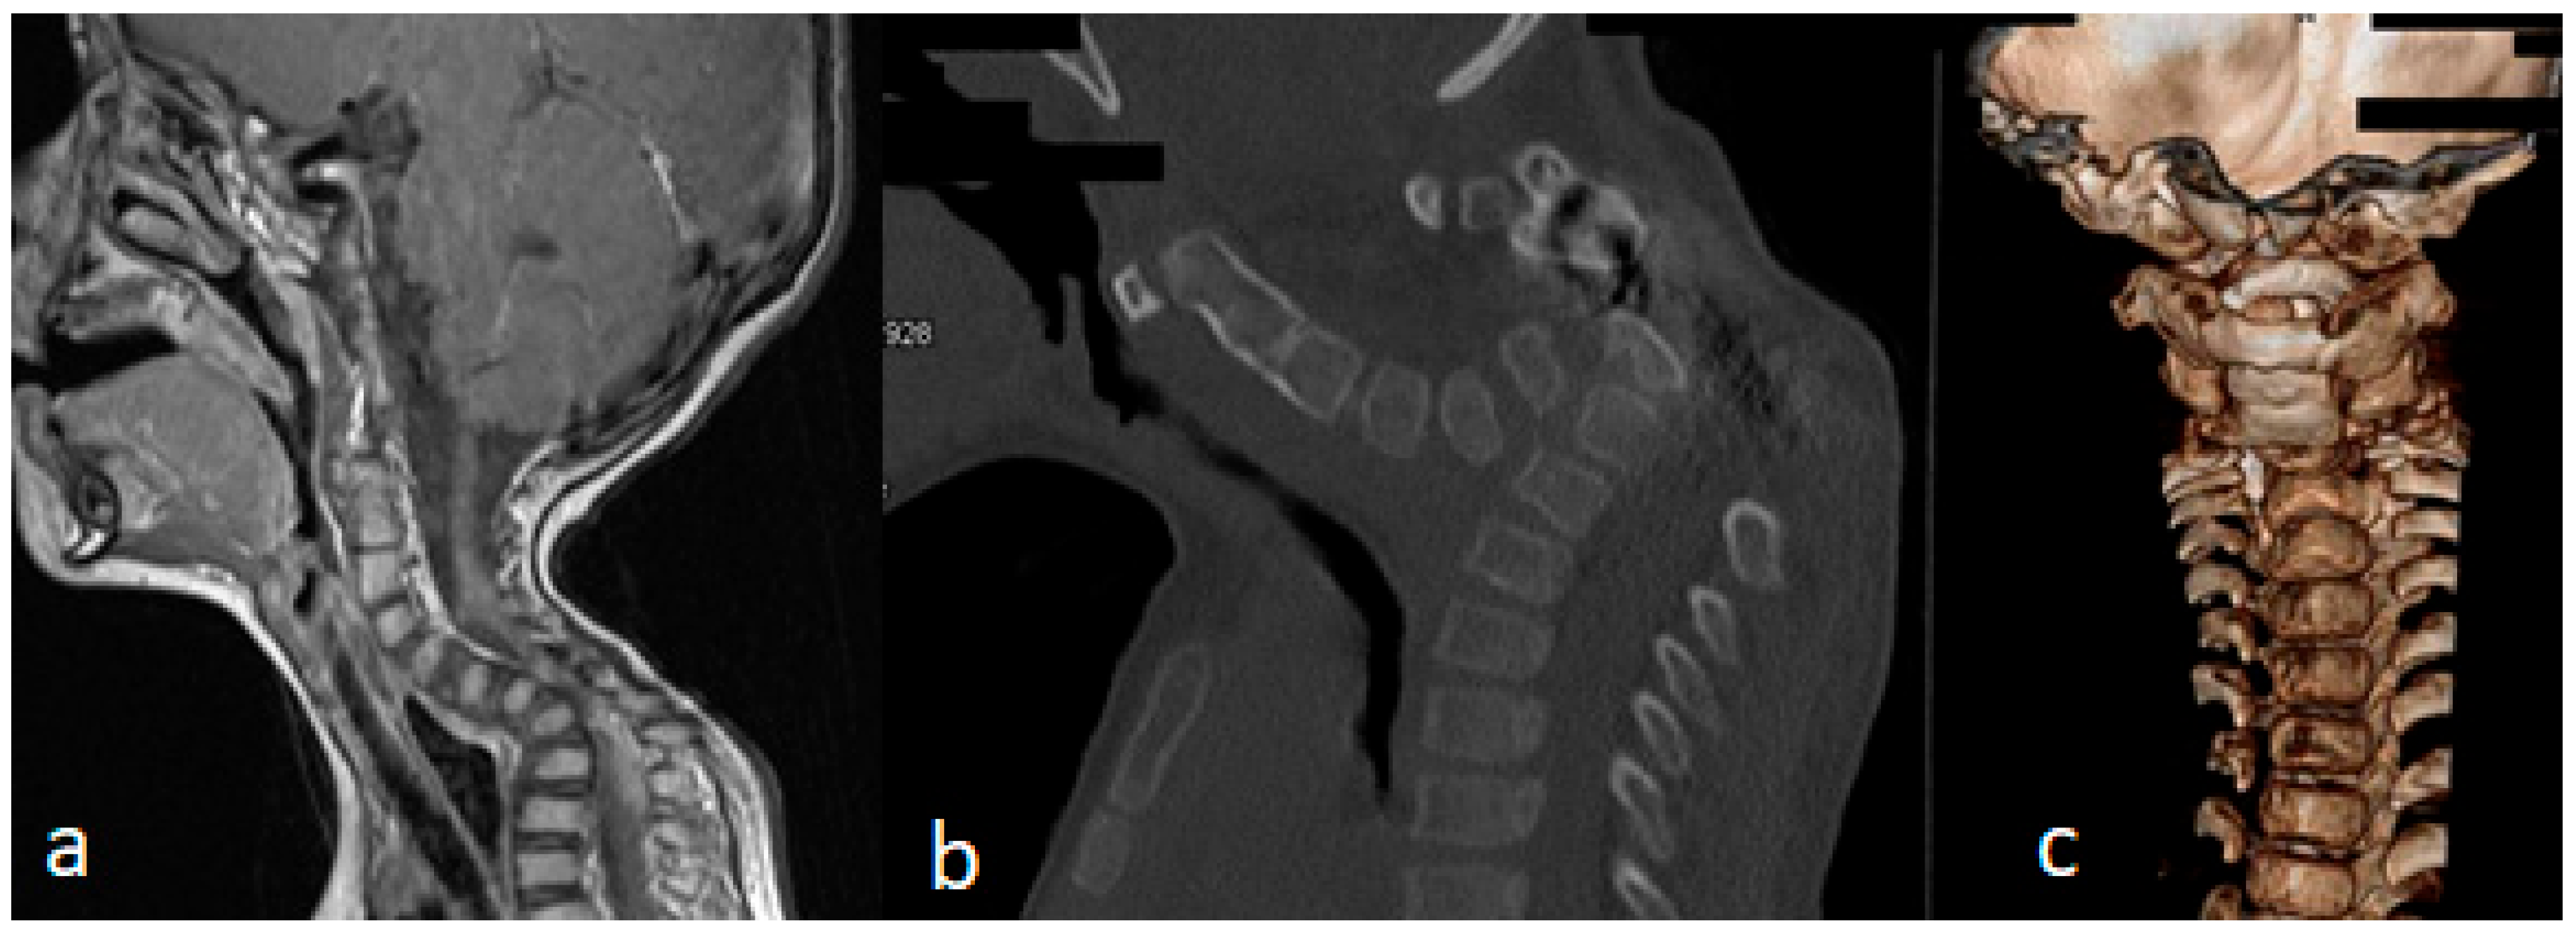

3.3. Acute-Angle Cervico-Thoracic Kyphosis in a Child with Larsen Syndrome

Acute-angle kyphosis (sharp angulation) presenting at birth or later on is almost always due to a congenital vertebral malformation. In this child, the deformity is purely kyphotic. Conservative treatment alone is of limited value in the management of congenital kyphosis, though some restrictions have to be considered to perform surgical interventions, especially when there is cardiopulmonary dysfunction, associated kidney anomalies, and neurological pathologies such as an Arnold–Chiari lesion, filum terminale syndrome, or diastematomyelia.

A sagittal cervico-thoracic MRI of a 2-year-old boy with Larsen syndrome showed cervico-thoracic kyphosis (Cobb’s angle of 90°) (Figure 5a). A sagittal cervico-thoracic 3D-reformatted CT scan of a 7-year-old child with Larsen syndrome showed hypoplastic anterior and posterior arches of the atlas fusion of C2-3 and hypoplasia and fragmentation of the seventh cervical spine (arrow) (Figure 5b). A 3D reconstruction CT scan of the same child showed fusion of C2-3 associated with hypoplastic vertebral bodies causing the development of acute cervico-thoracic kyphosis (Figure 5c).

Figure 5.

(a–c): A sagittal cervico-thoracic MRI of a 2-year-old boy with Larsen syndrome showed cervico-thoracic kyphosis (Cobb’s angle of 90°) (a). Sagittal cervico thoracic 3D-reformatted CT scan of a 7-year-old child with Larsen syndrome showed hypoplastic anterior and posterior arch of the atlas associated with fusion of C2-3, hypoplasia and fragmentation of the 7th cervical spine (arrow) (b). A 3D reconstruction CT scan of the same child showed fusion of C2-3 associated with hypoplastic vertebral bodies causing the development of acute cervico-thoracic kyphosis (c).